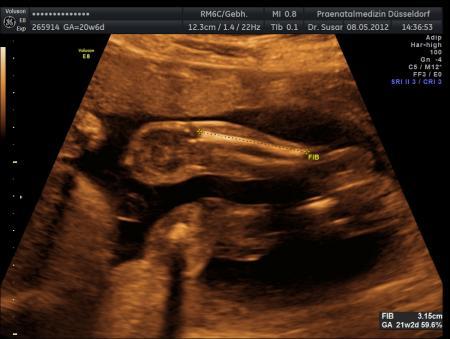

Gestern hatte ich total vergessen euch ein paar Bilder von meinem Würmchen zu zeigen.Wir haben zwar keines vom Gesicht bekommen,aber andere schöne waren dabei. Wollte euch mal ein paar zeigen :)

Bild zu Fotos von der FD gestern :) - Forum für September - Mamis

Und aller guten Dinge sind drei :P

Sind das immer die Beine bzw.Arme??? Hast duauch ein Gewicht und eine Maße bekommen??

Das sind die Beine. Also mein Kleiner war gestern 27 cm groß und knapp 500 gramm schwer. Nach dem Kopfumfang hab ich gar nicht gefragt vor Aufregung Da müsste ich noch mal in den Befund schauen, da steht es mit Sicherheit drin. Leider hat er wie gesagt seinen Kopf + Oberkörper immer schön weg gedreht wenn die Ärztin ein Foto knipsen wollte. Trotz rütteln und schütteln am Bauch. Zum Dank bekam ich nur ein paar saftige Tritte